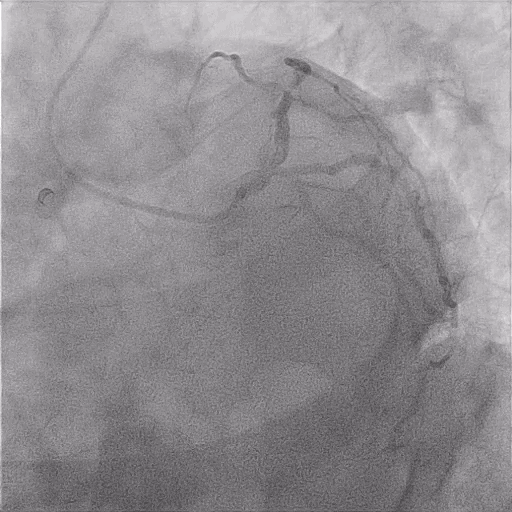

Fat Loss Cardio Guide Pdf High Intensity Interval Training Driving guidelines for arrhythmia syncope wide complex tachycardia – diagnosis wide complex tachycardia: management cardiac critical care aortic dissection cardiogenic shock cardiac tamponade. Developed through a rigorous review of medical literature, clinical practice guidelines define the role of diagnostic and therapeutic interventions—both noninvasive and invasive—in managing cardiovascular diseases.